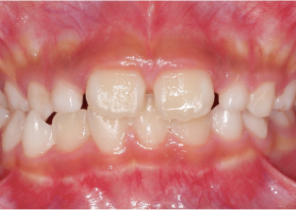

Report sul Caso 1

10 anni 0 mesi, 18 fasi di Invisalign Palatal Expander

Per gentile concessione della Dott.ssa Sandra Khong Tai

Pre espansione Invisalign Palatal Expander

Post espansione Invisalign Palatal Expander

Dopo il trattamento Invisalign First